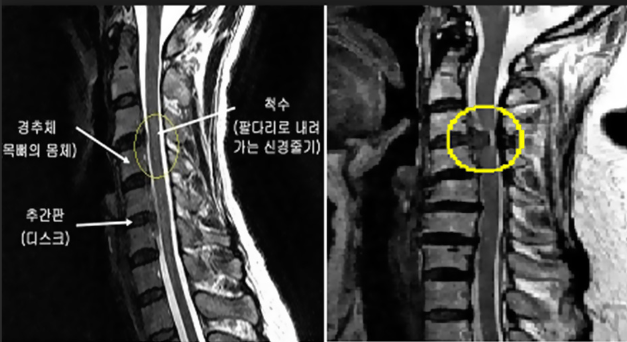

목, 즉 경추는 머리의 무게를 지탱할 뿐만 아니라 놀라운 가동 범위를 제공하는 복잡한 구조입니다. 목의 해부학적 구조를 이해하려면 이 중요한 부위를 구성하는 척추뼈, 추간판, 근육, 인대, 신경 및 혈관을 깊이 파고드는 것이 필요합니다.

목 해부학의 핵심에는 C1부터 C7까지 지정된 7개의 뼈가 서로 쌓여 있는 경추가 있습니다. 이 척추뼈는 목의 기능을 수용할 수 있도록 독특하게 구성되어 있습니다.

추간판은 각 척추체 쌍(C1과 C2 사이 제외) 사이에 위치하며 충격 흡수 장치 역할을 하고 척추에 유연성을 제공합니다. 각 디스크는 섬유테라고 불리는 질기고 섬유질의 외층으로 구성되어 있으며, 이는 속질핵으로 알려진 더 부드럽고 젤 같은 중심을 둘러싸고 있습니다.